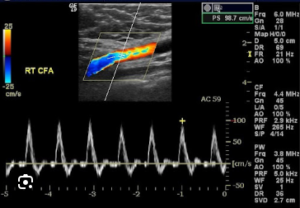

An Arterial Doppler (also called Arterial Color Doppler Ultrasound) is a non-invasive imaging test that uses sound waves to evaluate blood flow through the arteries in your arms, legs, or neck.

We use advanced color and spectral Doppler ultrasound systems that provide detailed visualization of blood flow and artery health.Experienced Radiologists & Sonographers